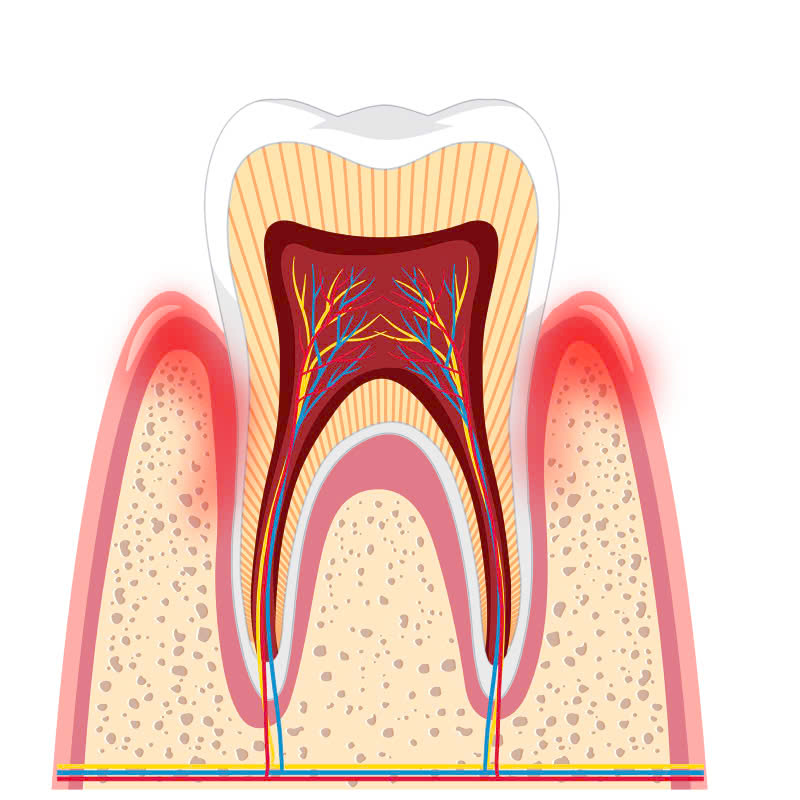

Túi nha chu là khoảng không gian rỗng giữa răng và khe nướu. Đây là nơi tích tụ mảng bám và vi khuẩn, dẫn đến tình trạng viêm nhiễm nha chu. Nếu không được điều trị kịp thời, tình trạng này có thể tiến triển, gây tổn thương mô mềm xung quanh và khiến nướu tuột khỏi chân răng.

Nạo túi nha chu là một phương pháp điều trị hiệu quả để loại bỏ mảng bám và vi khuẩn tích tụ trong túi nha chu. Qua đó, giúp giảm viêm nhiễm, ngăn chặn sự tiến triển của bệnh nha chu và cải thiện tình trạng sức khỏe răng miệng tổng thể.